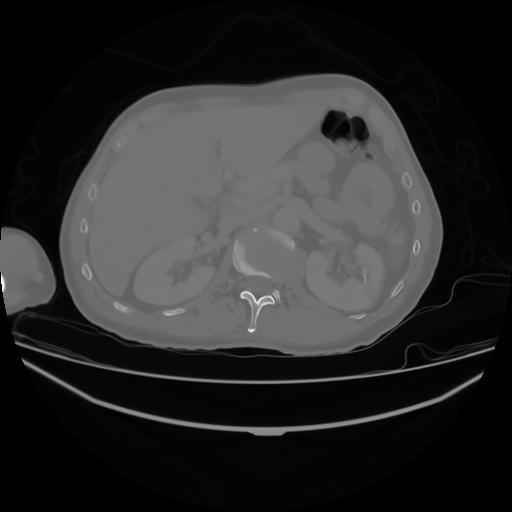

4 CUERPO,CE,Axial,3.0,CUERPO,,